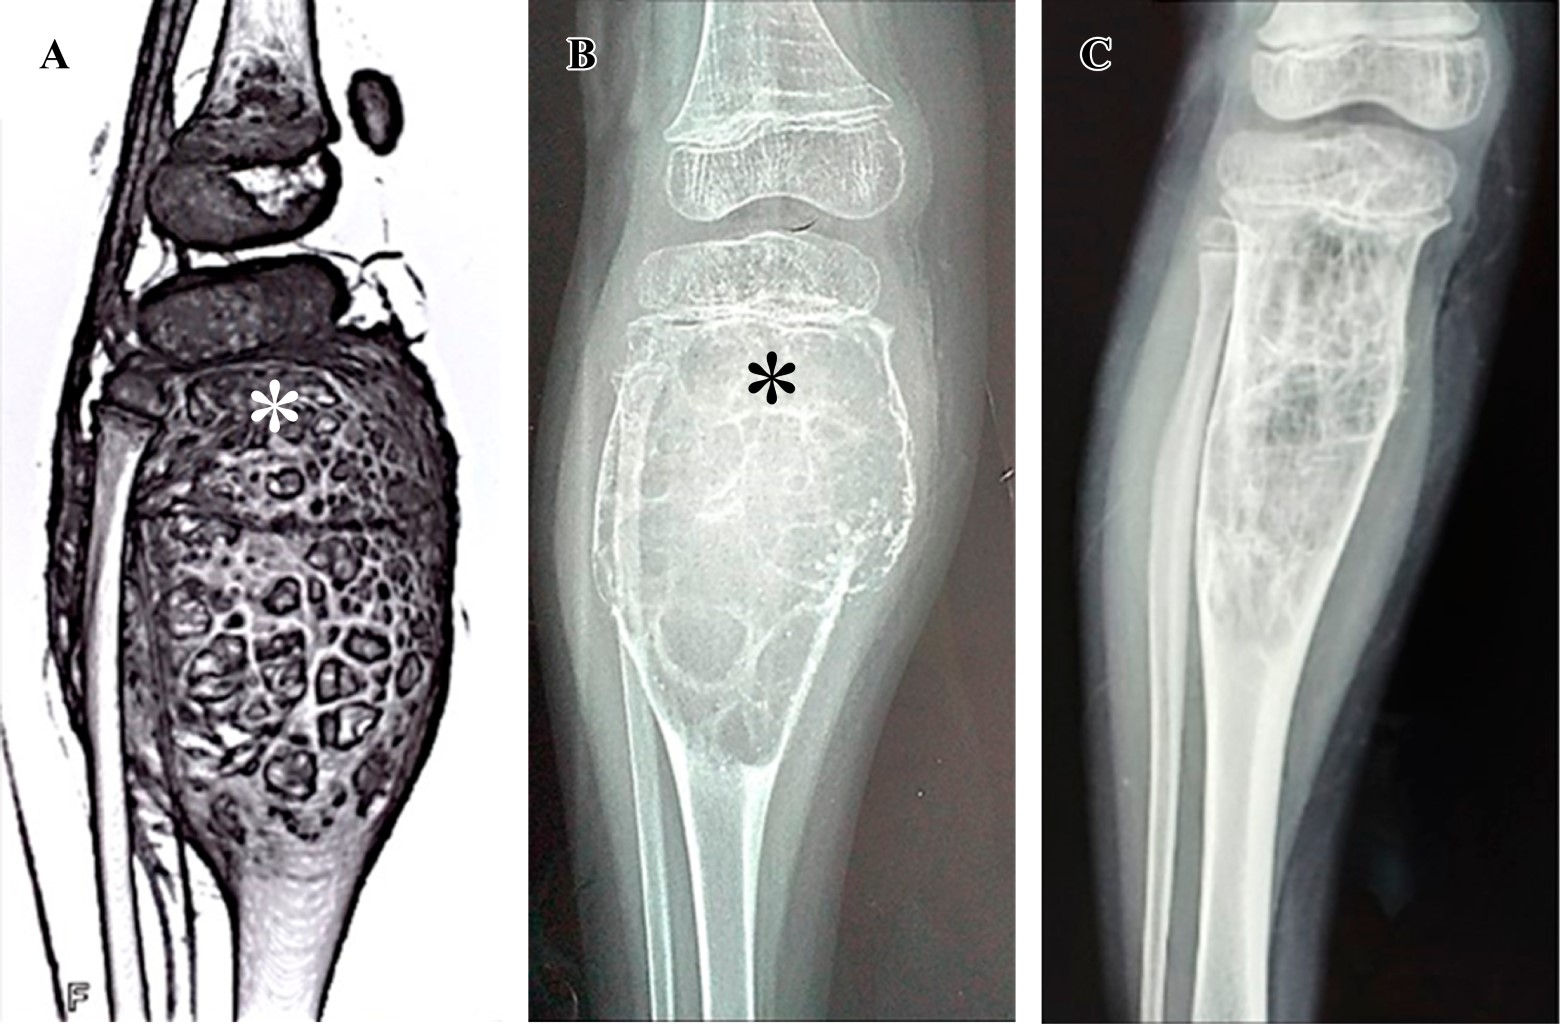

En los casos uno (Figura 1), cuatro, cinco, seis, siete y nueve se inyectaron 5 ml de polidocanol 3% en todas las sesiones. El primer paciente había recibido cirugía con curetaje óseo de la lesión un año antes por presentar recidiva del QOA, por lo que se optó por tratarle con escleroterapia. Al segundo paciente, en otra institución se le había realizado embolización de arterias aferentes del QOA, misma que fue inefectiva, motivo por el que se le realizó curetaje e injerto óseo; en menos de un año de seguimiento se evidenció recurrencia del QOA (Figura 2), razón por la cual se le indicó tratamiento con escleroterapia, recibió 5 ml de polidocanol 3% en la primera dosis y 10 ml en las dosis siguientes. En el tercero (Figura 3) y octavo pacientes se inyectaron 10 ml de la sustancia esclerosante en todas las sesiones. Número total de procedimientos: 44, cantidad de procedimientos por paciente: promedio 4.9 (DE: ± 2.0). Intervalo de dosis: promedio 11.54 semanas (DE: ± 14.57).

Figura 2